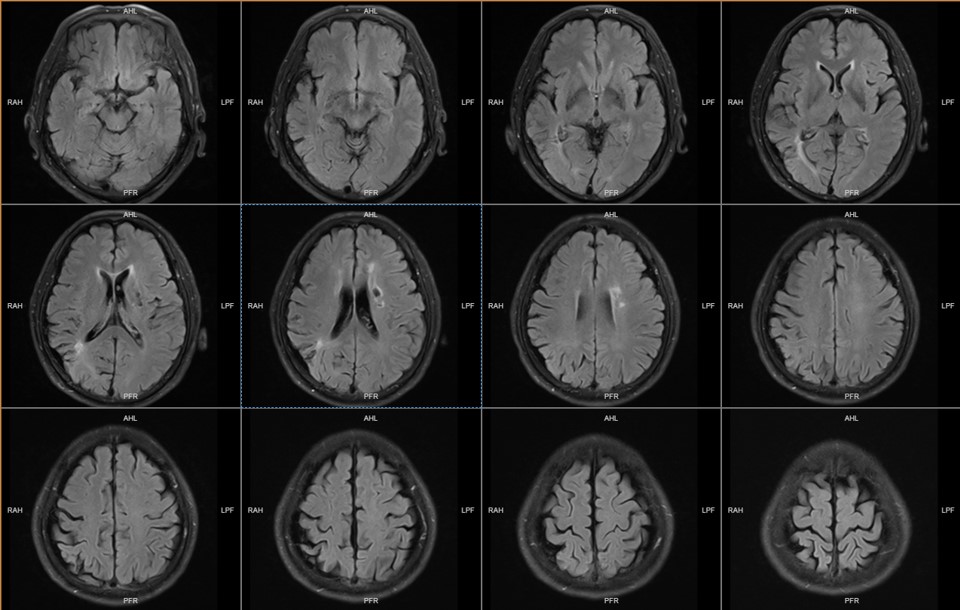

FLAIR显示左侧脑室旁陈旧性梗死灶;右侧脑室后角顶下小叶梗死灶。

DWI显示无急性梗死灶

MRA显示:右侧MCA不显影。

PWI显示:右侧颞叶、半卵圆区、顶下小叶MTT延长。

PWI显示:右侧颞叶、额叶下部、半卵圆区、顶叶PTT延长。